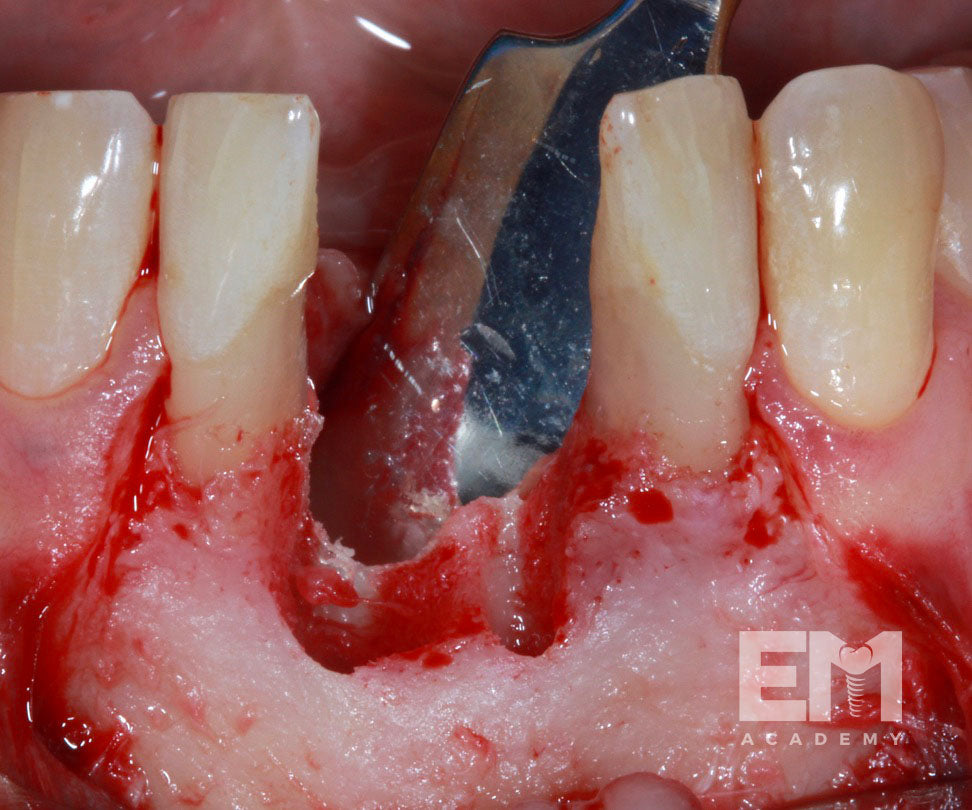

- Step by step techniques, including ridge splitting, GBR with resorbable barriers, titanium mesh, Ramus block harvest, autogenous particulate bone harvest, and Khoury technique

- Ridge splitting with implant placement

- GBR with resorbable barriers stabilized with sutures

- Ramus block harvest

- Khoury technique

- Labial and lingual flap release